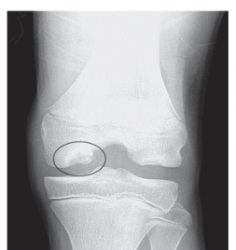

9

-Refer to the figure. What is the defect in the circle? Hint: This is the most common location for this lesion.

A) Osteochondritis dissecans

B) Fracture

C) Ewing's sarcoma

D) Osgood-Schlatter disease